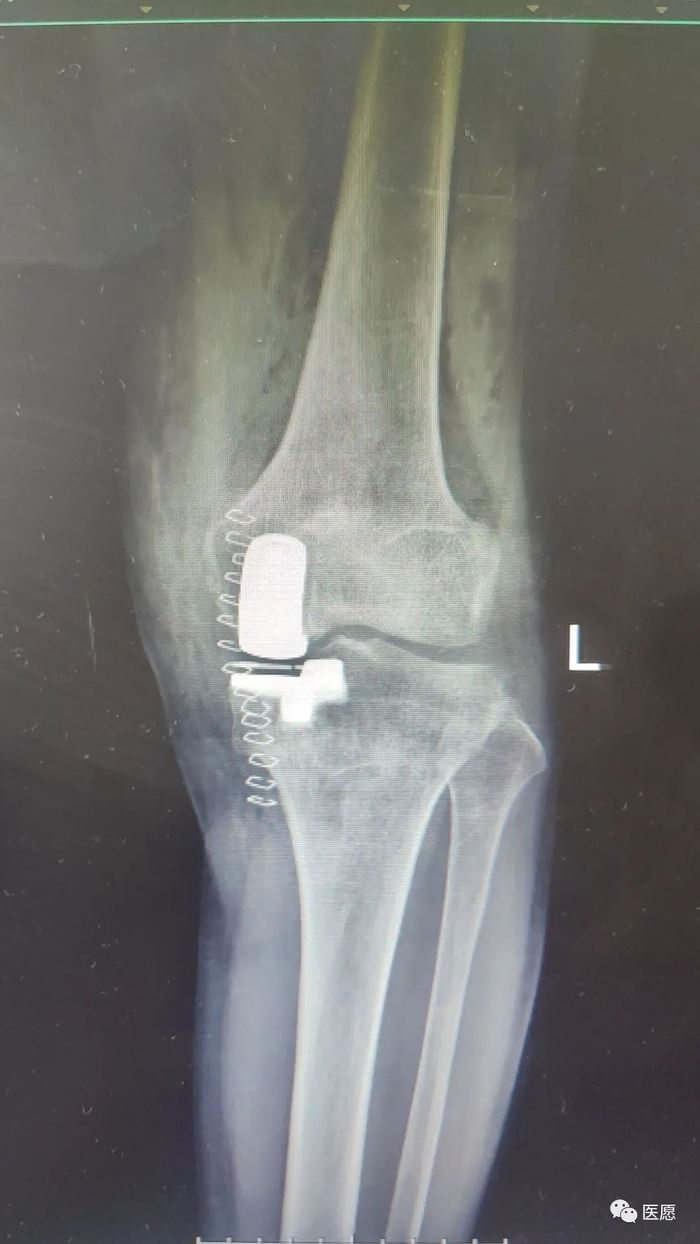

术后片

1

2